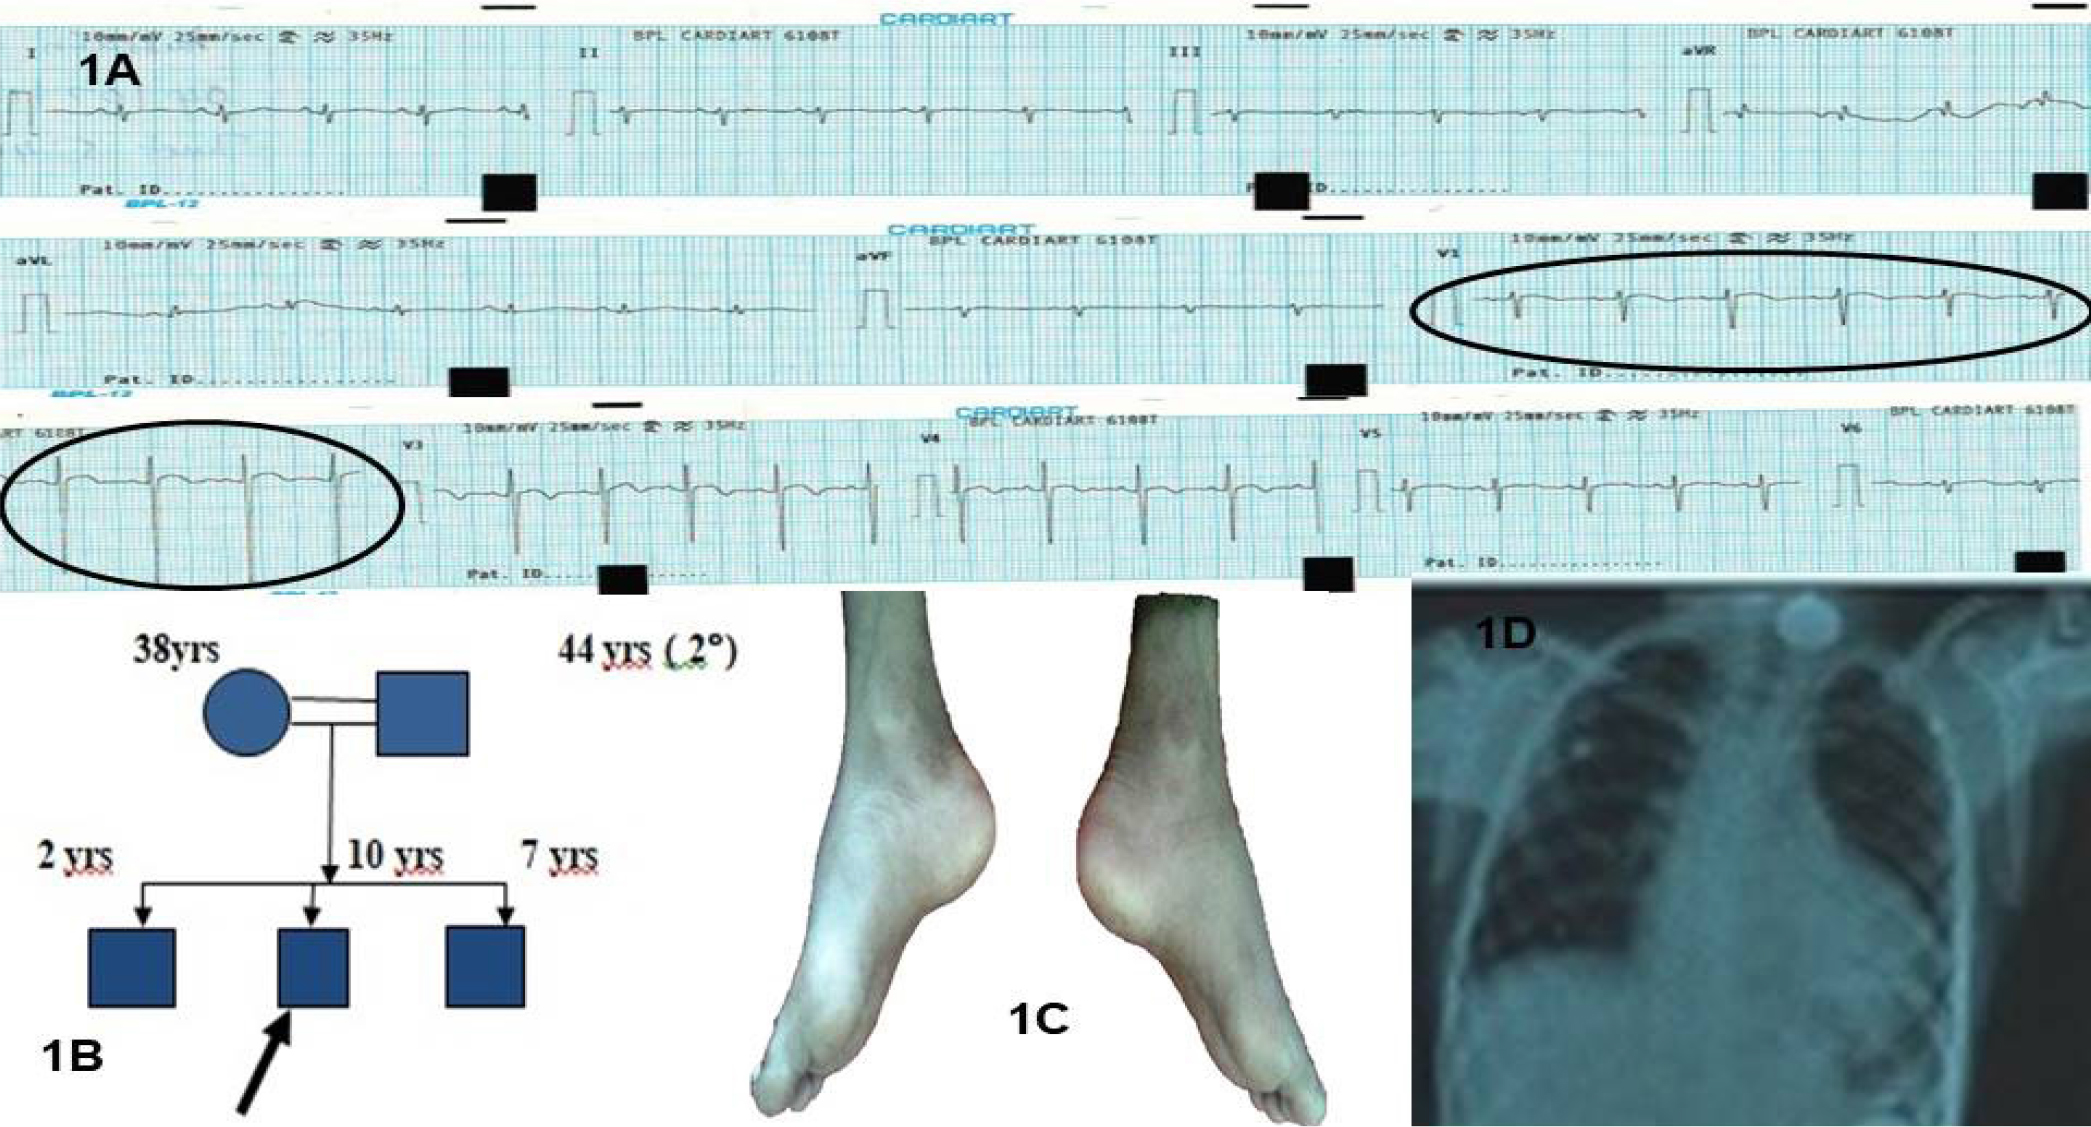

On evaluation, the child was conscious, tachypneic, with a pulse rate of 130 per min, His blood pressure was recorded 70/50 mmHg over the right upper arm. Physical examination revealed abnormal facies with pouting lips, protruding tongue, scoliosis, bilateral pes cavus (Figure 1C), Spina Bifida occulta. The systemic examination of the cardiovascular system revealed distant heart sounds and the lungs were clear on auscultation.

The Electrocardiogram (ECG) showed sinus tachycardia with a rate of 120 per min, an axis of -150°, and no significant ST-T changes, Left Ventricular Hypertrophy (LVH) by voltage criteria (Figure 1A). The chest x-ray showed cardiomegaly with an LV type of apex and clear lung fields and scoliosis of the thoracic spine (Figure 1D).

Figure 1: A) Admission electrocardiogram showing electrical alternans evident in Lead V1 and V2. 1B) Pedigree chart of the case. C) Bilateral pes cavus D) Chest x-ray showing moderate cardiomegaly with left ventricular type of apex. There is scoliosis with convexity to the left of the thoracic spine.